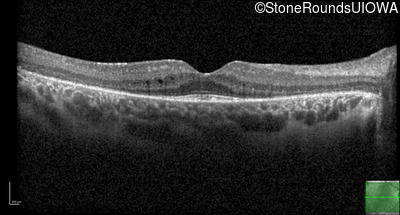

Age at visit: 9 years